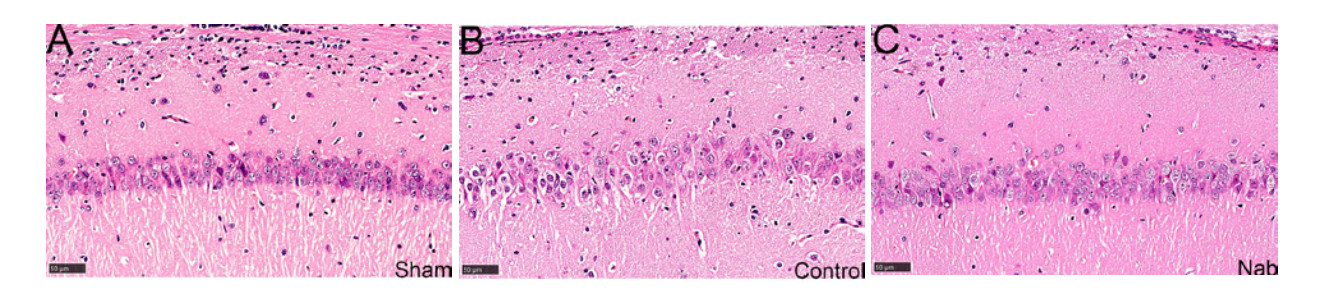

光镜下各组大鼠回肠上皮结构如图 1所示,图 1A为假手术组光镜下回肠组织结构。单纯心肺复苏组大鼠小肠组织肠黏膜显示黏膜结构严重紊乱,上皮细胞大面积剥离,固有层暴露伴显著水肿和炎性细胞浸润,可见绒毛缩短、倒伏甚至脱落并出现Gruenhagen间隙(箭头所示)(图 1B);丁酸钠组大鼠回肠绒毛高度部分恢复,排列较整齐,上皮连续性基本保留,仅局部轻微脱落,固有层水肿和炎症浸润减轻(图 1C)。电镜下,单纯心肺复苏组大鼠回肠上皮细胞间紧密连接出现间隙增宽(图 1E箭头所示),丁酸盐组则没有观察到此类现象(图 1F)。

| 注:图A~C分别为光镜下假手术组、单纯心肺复苏组及丁酸钠组回肠上皮组织情况(×200);图D~F分别为电镜下假手术组、单纯心肺复苏组及丁酸钠组回肠上皮组织情况(×50 000) 图 1 各组大鼠回肠上皮病理学评估 Fig 1 Pathological evaluation of ileal epithelium of rats in each group |